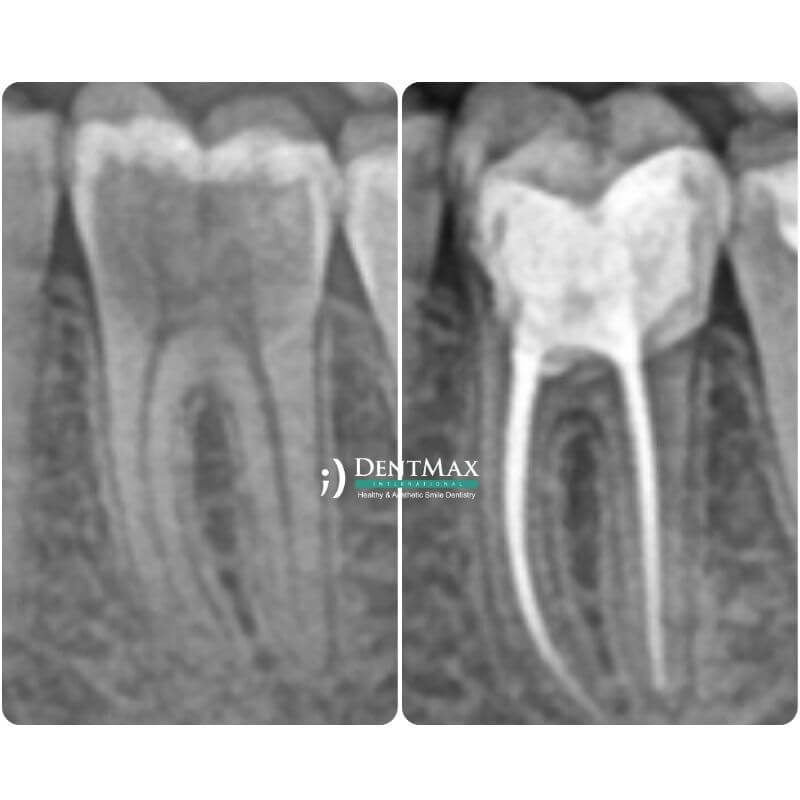

Лечение Каналов